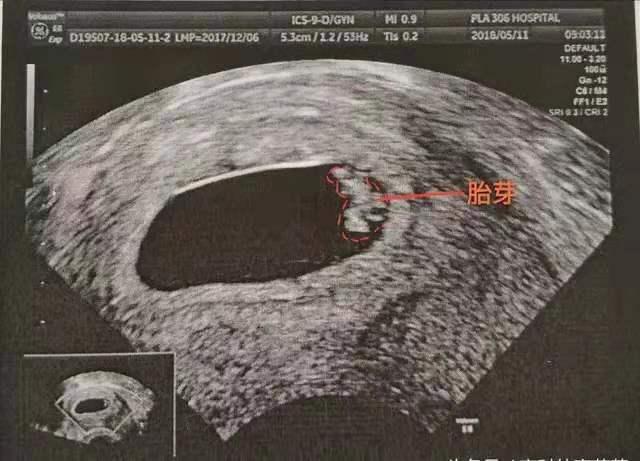

怀孕早期的B超检查,孕5周左右看是否怀孕、确认宫内,孕6周可以看到孕囊,孕7-8周B超可见胎心搏动。

怀孕8周去做做B超,可能看到胎儿已经有了胎心胎芽,但也可能看不到胎心胎芽,那能不能认为“看不到胎心就说明胎儿发育的不好呢”?

怀孕8周胎儿还看不到胎心,可能有两种情况:

1. 实际胎儿偏小

因为可能实际“胎儿偏小”,但这里说的“胎儿偏小”并不是发育不良导致的偏小,而是实际孕周偏小,还不到出现胎心的孕周,这是由于受精卵着床晚导致的。

比如孕妈平时月经不规律,或是记错末次月经的日子,都可能出现这种情况,因而先不必太过担心,可以再等等看,过一周后再去复查B超。